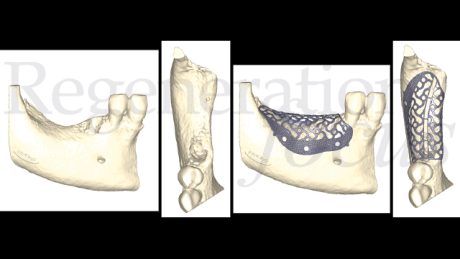

La pianificazione digitale ha guidato il design di una mesh patient-specific (Yxoss CBR® Protect) con spessore 0.6 mm, perforazioni di 1.2 mm, estensione 3 mm oltre i margini del difetto (Fig. 3).